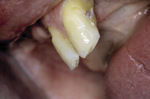

Podczas diagnostyki wczesnych zmian próchnicowych bardzo istotne jest rozróżnienie dwóch typów zmian: próchnicy początkowej i próchnicy zatrzymanej. (ryc. 2).

Oba ogniska znajdują się na powierzchni zęba przy zachowanej ciągłości szkliwa. Próchnica początkowa jest aktywnym ogniskiem choroby, które ulega progresji pod wpływem działania kwaśnych metabolitów bakteryjnych, natomiast próchnica zatrzymana jest rodzajem blizny tkankowej po wcześniejszym ognisku próchnicy i rzadko ulega zaostrzeniu. Różnicowanie tych zmian jest istotne przy podejmowaniu leczenia, ponieważ tylko próchnica początkowa będzie ulegała remineralizacji.